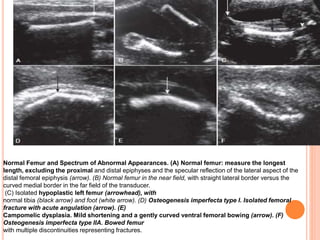

Normal Femur and Spectrum of Abnormal Appearances. (A) Normal femur: measure the longest

length, excluding the proximal and distal epiphyses and the specular reflection of the lateral aspect of the

distal femoral epiphysis (arrow). (B) Normal femur in the near field, with straight lateral border versus the

curved medial border in the far field of the transducer.

(C) Isolated hypoplastic left femur (arrowhead), with

normal tibia (black arrow) and foot (white arrow). (D) Osteogenesis imperfecta type I. Isolated femoral

fracture with acute angulation (arrow). (E)

Campomelic dysplasia. Mild shortening and a gently curved ventral femoral bowing (arrow). (F)

Osteogenesis imperfecta type IIA. Bowed femur

with multiple discontinuities representing fractures.

(G) Hypophosphatasia. Severe micromelia (relatively broad metaphysis, short

diaphysis)

. (H) Thanatophoric dysplasia. Curved, “telephone receiver” femur.